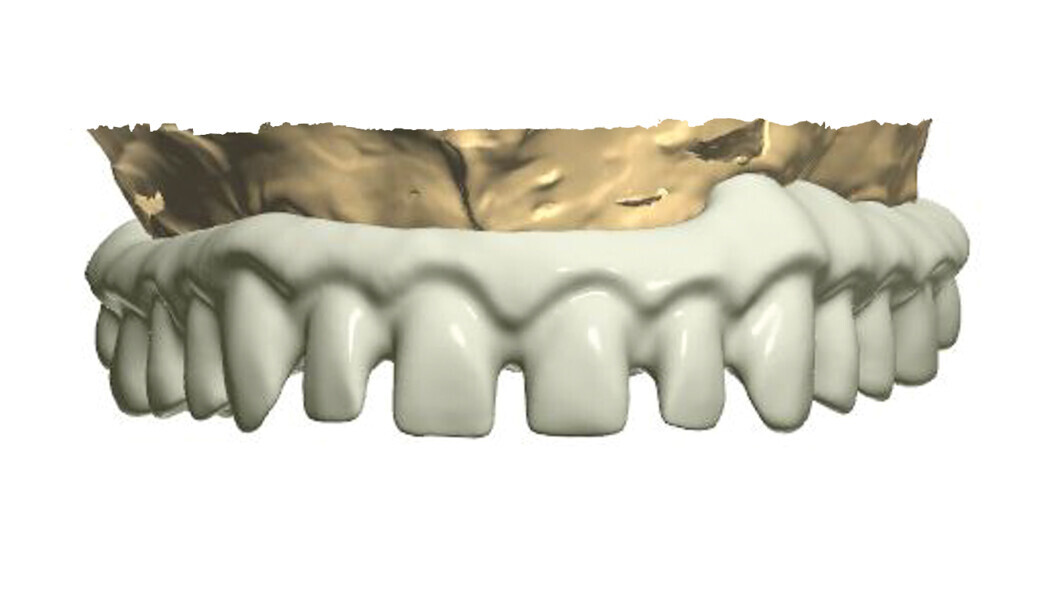

Fig. 1: A virtual image of a scanned model with abutments and telescopic crowns.